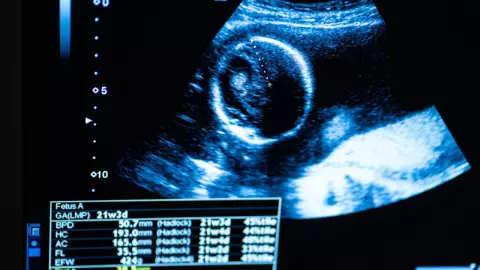

Sin embargo, tras someterla a una tomografía, el personal médico descubrió la presencia de un feto calcificado, una condición conocida como litopedia. Este fenómeno ocurre cuando un óvulo fertilizado se desarrolla fuera del útero, resultando en la muerte del feto y su posterior calcificación.

Con la esperanza de aliviar la infección y los problemas de salud de la paciente, se decidió llevar a cabo una operación para extirpar el feto calcificado, que según estimaciones médicas, tenía más de 30 años dentro del cuerpo de la anciana.

La litopedia es una condición médica extremadamente rara en la cual un óvulo fertilizado se desarrolla fuera del útero, generalmente en la cavidad abdominal, y muere debido a la falta de suministro de nutrientes. Lo que distingue a la litopedia es que, en lugar de ser reabsorbido por el cuerpo o expulsado, el feto se calcifica con el tiempo, convirtiéndose en una masa dura similar a una piedra.

Este fenómeno puede pasar desapercibido durante años o décadas, hasta que provoque síntomas como dolor abdominal, infección o complicaciones más graves que requieran atención médica urgente.